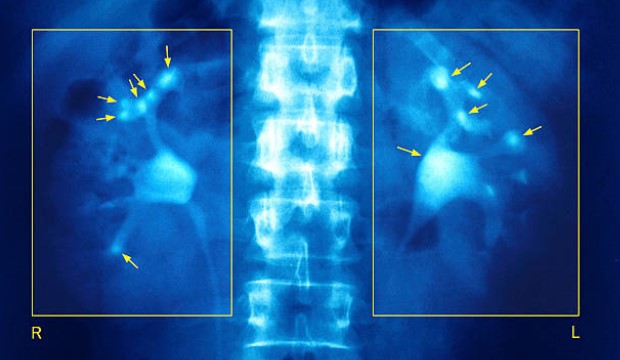

Létezik egy szinte elviselhetetlen deréktáji, az alhas, a hát, a láb irányába sugárzó fájdalom, ami az esetek 75 százalékában szinte egyik óráról a másikra megszűnhet. Ez a vesekő okozta vesegörcs.